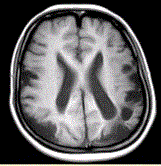

问题 女性,22岁。癫痫发作及智力异常。MRI显示见下图。 有关该病的描述正确的是(提示MRA所示如图。)

选项 A.双侧颈内动脉及其分支部分闭塞 B.双侧大脑后动脉狭窄、部分闭塞 C.颅底可见大量侧支循环形成 D.血管未见明显异常 E.双侧椎动脉显示清晰 F.双侧颈内动脉显示清晰

答案 ABC